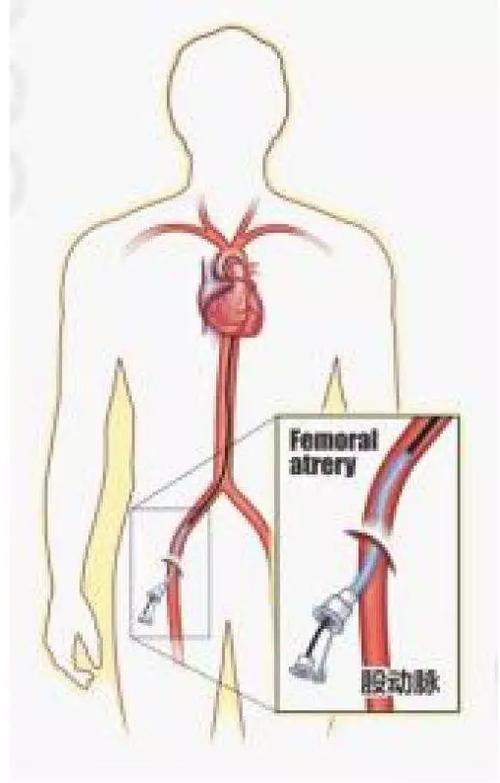

揭秘手术台丨冠脉造影原来是这么做的!

冠状动脉造影术

【医学科普】带你一起进入冠脉造影和心脏支架植入现场

冠状动脉造影

(冠状动脉造影检查)

心脏造影检查血管堵塞多少做支架

【专病专讲】冠心病之冠脉造影检查

心脏造影_什么情况需要做心脏造影

心脏造影有风险不能随便做?出现这几种情况,该检查一下心脏

得了冠心病,到底做心脏造影还是cta,了解这些

冠脉造影医保报销比例冠县社保局【心科普】为什么要做冠脉造影检查